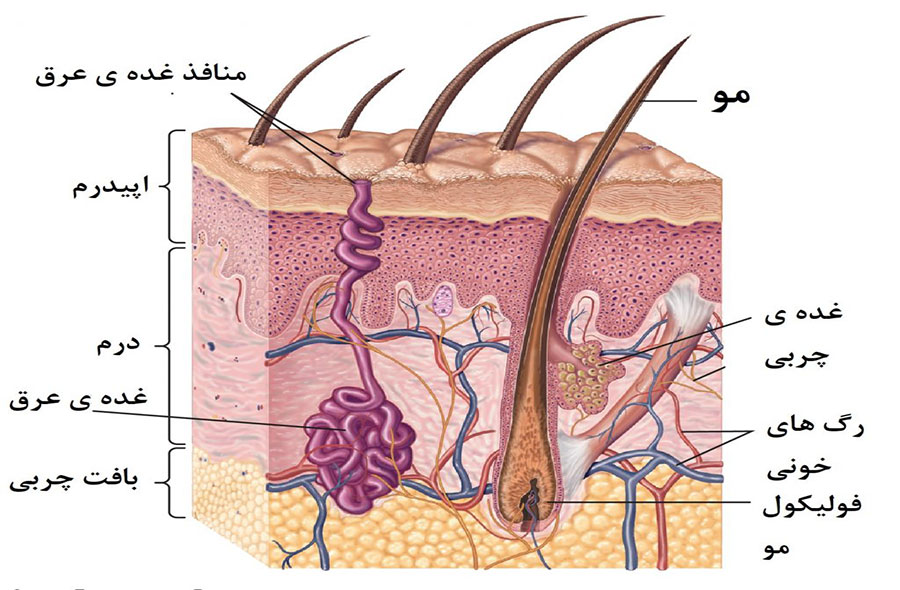

قیمت: 32٬000 تومان - دسته بندی فایل: پاورپوینتپاورپوینت بافت پوست

فروش ویژه پاور پوینت حرفه ای بافت پوست با تخفیف استثنایی فقط 49 هزار تومان تعداد اسلاید: 15 اسلاید